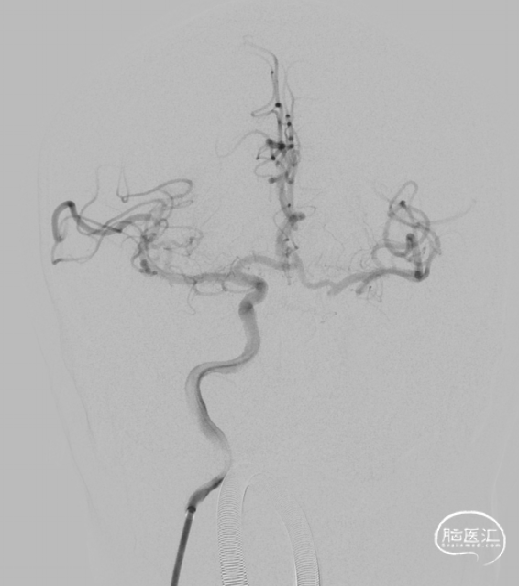

术前DSA

M1闭塞消失 溶栓后血栓移位?M2下干取栓?

以8F导引导管做支撑送入右侧颈内C1段,同轴送入132cm-AXS Catalyst-6中间导管、150cm-0.021-Trevo Pro 18微导管、200cm-0.014-Synchro2微导丝;CAT-6送至M1段闭塞处;微导管送入右侧大脑中动脉M2段后,1ml注射器回抽见血液回流再手动造影。